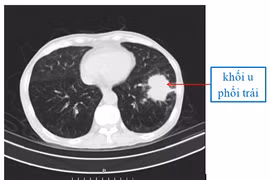

(khoahocdoisong.vn) - Muốn tầm soát ung thư phổi cần đến bệnh viện để kiểm tra lâm sàng ngực, kiểm tra hạch bạch huyết ở cổ, nếu có nghi ngờ ung thư phổi, bác sĩ sẽ chụp CT Scan ngực liều thấp, đây là một xét nghiệm sàng lọc được khuyến cáo.